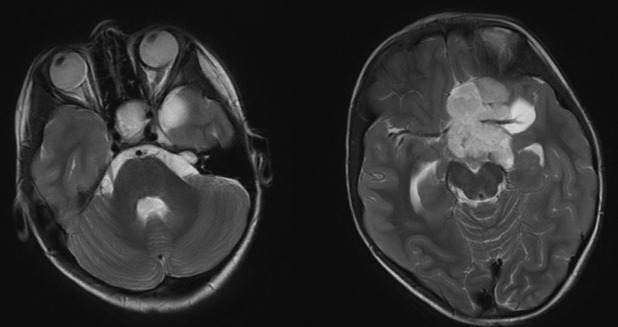

图 8 两例视神经胶质瘤影像学表现:a 和 b 为一例,双侧视神经肿胀,可见强化改变,累及视交叉;c 和 d 为另一例,可见左侧视神经迂曲改变,结果证实为视神经胶质瘤

视神经胶质瘤是发生于视神经内胶质细胞的良性肿瘤,可沿视神经向颅内蔓延,可见于球后视神经、视交叉、下丘脑、视束至外侧膝状体通路上的任何部位。该病好发于 10 岁以内儿童,部分与神经纤维瘤病伴发,疑有遗传倾向。